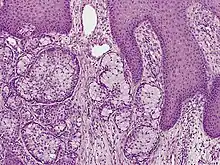

| Eccrine carcinoma, alveolar type | |

Eccrine carcinoma is a rare skin condition characterized by a plaque or nodule on the scalp, trunk, or extremities.[1]: 669 It originates from the eccrine sweat glands of the skin, accounting for less than 0.01% of diagnosed cutaneous malignancies.[2] Eccrine carcinoma tumors are locally aggressive, with a high rate of recurrence. Lack of reliable immunohistochemical markers and similarity to other common tumors has made identification of eccrine carcinoma difficult.[2]

A skin biopsy is the most common test used to diagnose eccrine carcinoma.[2] The biopsy will detect growth of new or abnormal tissue. Another test that can be performed is using immunohistochemistry, but it is inconsistent.[2] Markers used to detect eccrine carcinoma consist of carcinoembryonic antigen, progesterone receptors, estrogen receptors, epithelial membrane antigen, pancytokeratins, and cytokeratin 7.[5][6]